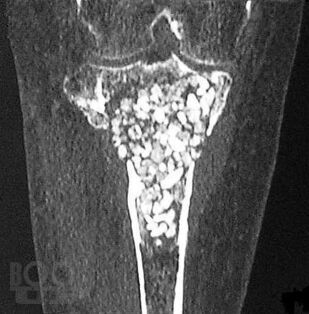

В настоящей монографии в сравнительном аспекте рассматриваются диагностические и дифференциально-диагностические возможности сцинтиграфии с неспецифическим туморотропным радиофармацевтическим препаратом и индикатором воспалительных процессов 199Tl-хлоридом. Авторами показана высокая эффективность сцинтиграфии с 199Tl-хлоридом в неспецифической индикации и дифференцильной диагностике опухолевых и воспалительных процессов опорно-двигательного аппарата, органов грудной клетки и прочих локализаций, приводятся диагностические и дифференциально-диагностические критерии этих процессов.